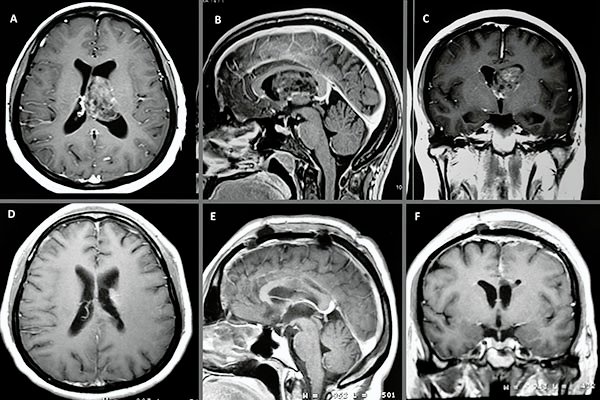

En la RM de encéfalo control, realizada 20 días luego de la cirugía, se observa huella de callosotomía anterior sin lesión focal intraventricular residual aparente (fig. 4).

Figura 4:

A, B y C) Cortes axial, sagital y coronal pre quirúrgicos ponderados en T1 con contraste. D, E y F) Cortes axial, sagital y coronal post quirúrgicos ponderados en T1 con contraste.